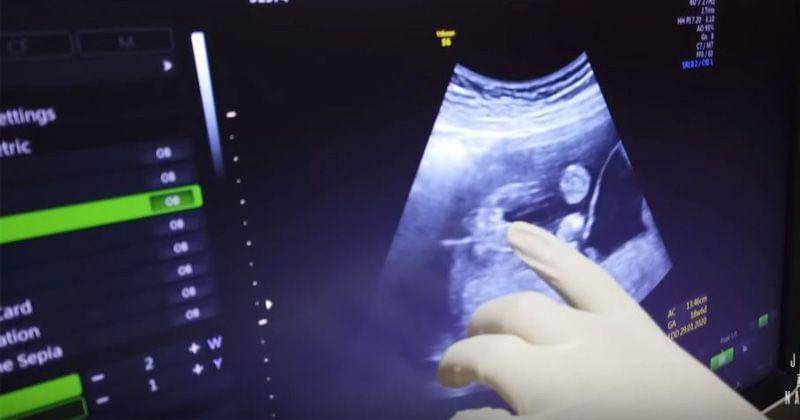

1. Hasil USG pertama terlihat bayi perempuan

Saat melakukan pemeriksaan, dokter menyebut kalau kondisi bayi Syahnaz sehat dan sudah berusia 19 minggu.

Kemudian, dokter pun mengungkapkan jenis kelamin bayi kembar dari pasangan yang menikah pada 21 April 2018 lalu itu.

"Dapat anak cewek satu," ujar dr. Nando.

Sang dokter pun menegaskan bahwa salah satu dari calon bayi kembar Syahnaz dan Jeje berjenis kelamin perempuan.

2. Tak lama, terlihat hasil USG anak laki-laki

Setelah mengetahui jenis kelamin bayi perempuannya, sang Dokter kembali menyebutkan bahwa Syahnaz dan Jeje juga akan memiliki anak laki-laki.

"Ini sepasang, laki-laki dan perempuan. Asyik banget," ujar dokter.

"Satu lagi memang beneran cowok. Itu jelas banget cowok," ungkap sang Dokter.

Saat melakukan USG, dokter Nando pun juga sempat menjelaskan kondisi kesehatan sang Janin di dalam perut Syahnaz.

Di monitor terlihat dan terdengar jelas detak jantung bayi kembar Syahnaz yang normal dan sehat. Hal tersebut pun diungkapkan oleh dokter kandungan Syahnaz tersebut.

"Wah besar sekali detaknya," ungkap sang Dokter.

Setelah mengecek detak jantungnya, dokter Nando pun kemudian mengecek ukuran besar janin kembar Syahnaz.

"Ukurannya juga mantap, nih," ungkapnya lagi.